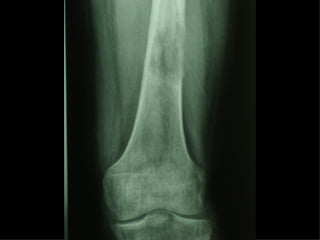

Dal Gennaio 2000 al Dicembre 2005 27 placche LISS di femore

INDICAZIONI COMUNI Fratture sovracondiloidee Fratture intercondiliodee Fratture diafisarie distali PARTICOLARI Fratture con grave osteoporosi Fratture periprotesiche

F, 68 y